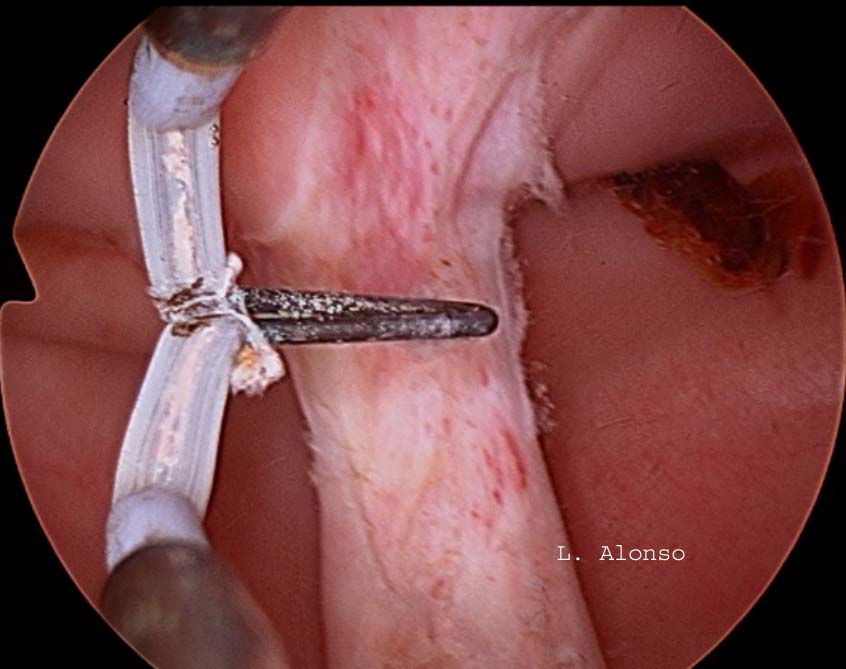

The surgical technique with preservation of the cervical septum was described in a series of 21 patients by Rock [Rock, J.A., et al. (1999). “Hysteroscopic metroplasty of the Class Va uterus with preservation of the cervical septum.” Fertil Steril 72 (5): 942-945.] The description of the technique is as follows: after cervical dilatation, a Foley catheter or a dilator is inserted into one of the cavities that serve as a guide for the section of the body part of the septum. Subsequently, the resectoscope was inserted with a Collin’s loop in the other cavity and the intrauterine septum was incised at the supracervical level.

The arguments favoring to preserve the cervical septum are that it is a vascular structure whose section could result in massive intraoperative bleeding and that the transection of the cervical septum could cause cervical incompetence, which would require performing a cerclage if the patient were to conceive.

The first publication regarding the section of the cervical septum was reported by Vercellini [Vercellini, P., et al. (1994). “A modified technique technique for correction of the complete septate uterus.” Acta Obstet Gynecol Scand 73 (5): 425-428.] Who performed the section of the cervical septum with Metzenbaun scissors in 7 patients in which they had great difficulty in creating the initial communication between the two endometrial cavities. Later, they compared the results of these patients with another group of 9 patients in whom this intracervical septum was left intact. There were no intraoperative or obstetric complications related to the section of the cervical septum. No cerclage was performed on any of the patients.